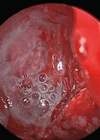

Endoscopic excision of cholesteatoma

In this article Vikranth Visvanathan describes an exciting development on the use of endoscopic technology in complex otological practice. Transcanal endoscopic ear surgery (TEES) is rapidly evolving as a recognised method of addressing middle ear and mastoid pathology. Since its...